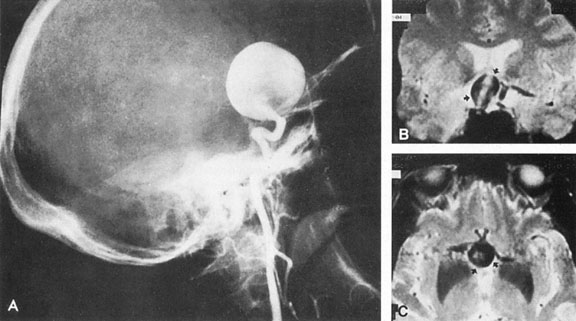

Most such aneurysms expand upward and forward, becoming located primarily anteriorly (Fig. 4). The optic nerves rise upward form the optic canal and may be inclined at a 45-degree angle such that the chiasm is more superiorly, as well as posteriorly, placed. It may be expected that uniocular ipsilateral visual loss would occur and progress before the contralateral field is involved because of chiasmal compression and before opposite nerve damage ensues. Although rapid visual loss has been reported, a longer duration (even years) is the rule. Rarely, the aneurysm may be more posteriorly placed or the chiasm more anteriorly fixed, resulting in initial involvement of the optic tract.20

Fig. 4. Giant suprasellar (supraclinoidal) aneurysms. A: Carotid arteriogram (lateral view) shows a huge aneurysm of the internal carotid artery in a 59-year-old woman with progressing visual loss. Coronal (B) and axial (C) magnetic resonance imaging sections of a similar case. Note partial thrombus formation (TR, 2100 ms; TE, 80 ms).

Large aneurysms also arise from or involve the origins of the middle or anterior cerebral arteries, and they may precisely mimic a slowly growing suprasellar neoplasm. Similarly, large aneurysms of the supraclinoid carotid can simulate a pituitary tumor,7 including prolactinemia.21 Aneurysms may mimic other masses, and thus underscores the need for MRI or arteriography in the evaluation of some sellar or parasellar syndromes.